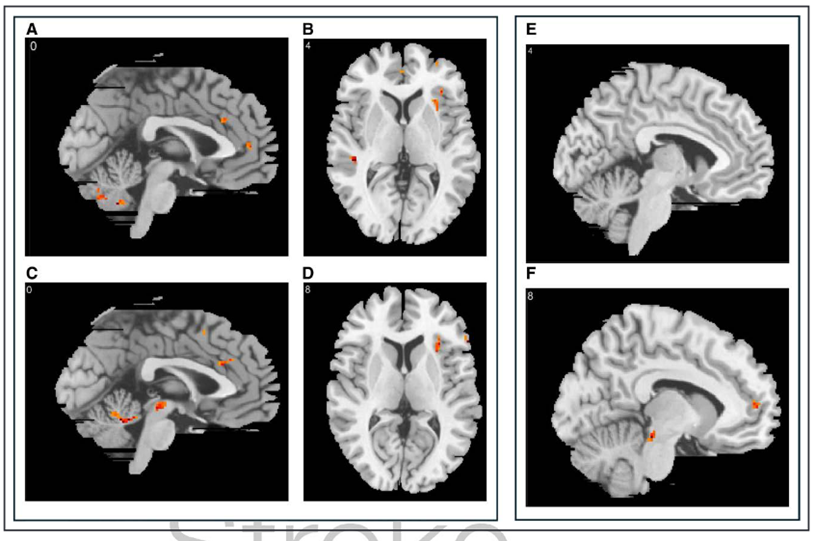

4.2 中风幸存者自愿收缩的充盈期(P4P5)与P3对比

对比P4_VOLP3_VOLP5_VOLP3_VOL发现,在P4期间双侧前部和左侧背侧扣带回皮质(ACC)激活;在P5期间右侧岛叶、双侧背侧ACC、右侧中部扣带回皮质激活。在此期间还观察到小脑激活(图2)。

中风幸存者意志性逼尿肌收缩前的脑活动图

中风幸存者自主逼尿肌收缩前P4(顶部,AC)和P5(底部,DF)期间血氧水平依赖性效应变化的代表性矢状和轴向图像。注意P4AC)期间头端前扣带皮层(ACC)的激活,以及P5期间头端ACCDE)和岛叶(F)的激活。